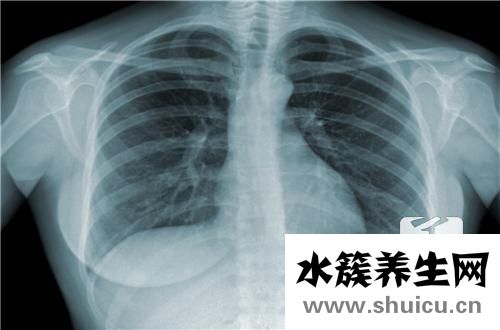

?結核病是一個普遍的問題,它將對人的身體造成很大的壓力,結核病的原因很多,通常與病理因素有關,許多人的肺功能本身是正常的,但是由于長期吸入這些非生態 細菌會產生巨大的肺泡,導致病毒吞噬,并逐漸導致肺部感染。 此外,由于空氣質量差,現在在許多地區,它們經常留在化工廠旁邊,并長時間吸入。 廢氣和溫暖的環境是導致結核菌的關鍵因素。 一旦出現結核菌,就必須對其進行隔離和治療,以防止其傳播給家人或親人。

引起肺結核為最多。因腸道中有大量正常菌群寄居,結核分枝桿菌必須通過競爭才能生存并和易感細胞粘附。肺泡中無正常菌群,結核分枝桿菌可通過飛沫微滴或含菌塵埃的吸入,故肺結核較為多見。 1、肺部感染:由于感染菌的毒力、數量、機體的免疫狀態不同,肺結核可有以下兩類表現。

(1)原發感染:多發生于兒童。肺泡中有大量巨噬細胞,少數活的結核分枝桿菌進入肺泡即被巨噬細胞吞噬。由于該菌有大量脂質,可抵抗溶菌酶而繼續繁殖,使巨噬細胞遭受破壞,釋放出的大量菌在肺泡內引起炎癥,稱為原發灶。初次感染的機體因缺乏特異性免疫,結核分枝桿菌常經淋巴管到達肺門淋巴結,引起肺門淋巴結腫大,稱原發綜合征。此時,可有少量結核分枝桿菌進入血液,向全身擴散,但不一定有明顯癥狀(稱隱性菌血癥);與此同時灶內巨噬細胞將特異性抗原遞呈給周圍淋巴細胞。感染3~6周,機體產生特異性細胞免疫,同時也出現超敏反應。病灶中結核分枝桿菌細胞壁磷脂,一方面刺激巨噬細胞轉化為上皮樣細胞,后者相互融合或經核分裂形成多核巨細胞(即朗罕巨細胞),另一方面抑制蛋白酶對組織的溶解,使病灶組織溶解不完全,產生干酪樣壞死,周圍包著上皮樣細胞,外有淋巴細胞、巨噬細胞和成纖維細胞,形成結核結節(即結核肉芽腫)是結核的典型病理特征。感染后約5%可發展為活動性肺結核,其中少數患者因免疫低下,可經血和淋巴系統,播散至骨、關節、腎、腦膜及其他部位引起相應的結核病。90%以上的原發感染形成纖維化或鈣化,不治而愈,但病灶內常仍有一定量的結核分枝桿菌長期潛伏,不但能刺激機體產生免疫也可成為日后內源性感染的淵源。

(2)原發后感染:病灶亦以肺部為多見。病菌可以是外來的(外源性感染)或原來潛伏在病灶內(內源性感染)。由于機體已有特異性細胞免疫,因此原發后感染的特點是病灶多局限,一般不累及鄰近的淋巴結,被纖維素包圍的干酪樣壞死灶可鈣化而痊愈。若干酪樣結節破潰,排入鄰近支氣管,則可形成空洞并釋放大量結核分枝桿菌至痰中。